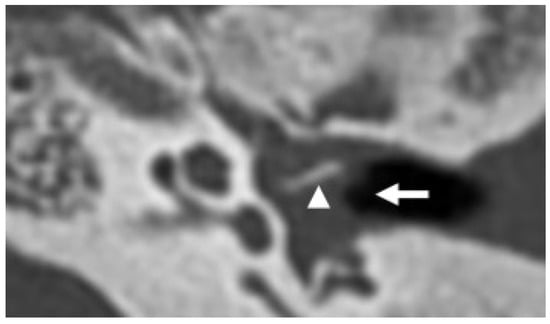

3.2. Bony Dehiscence